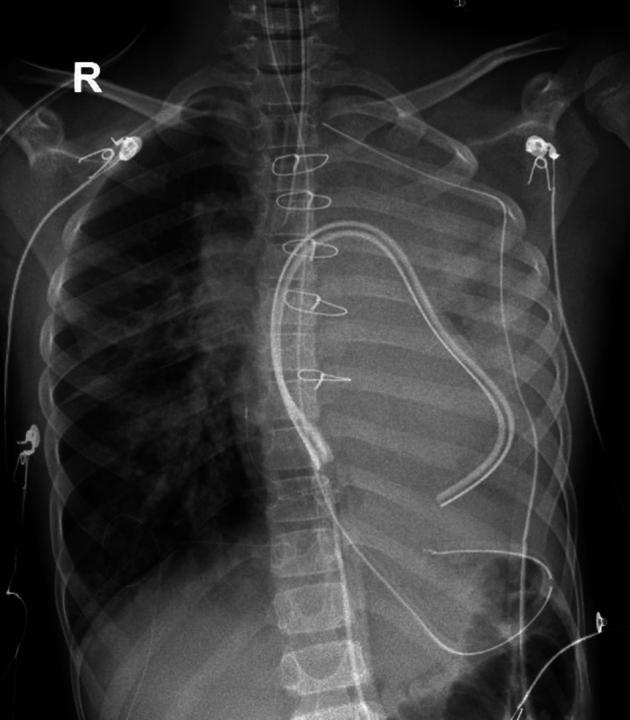

Diastolic dysfunction manifesting as acute plastic bronchitis after Warden procedure.

Pasternack Daniel M, Martinez Michael J, McKinstry Jacqueline, Singh Rakesh, Saharan Sunil, Muise Eleanor D, Mosca Ralph, Kumar T K Susheel

JTCVS Tech. 2024 Apr 3;25:153-156. doi: 10.1016/j.xjtc.2024.03.018. eCollection 2024 Jun.

Abstract

摘要